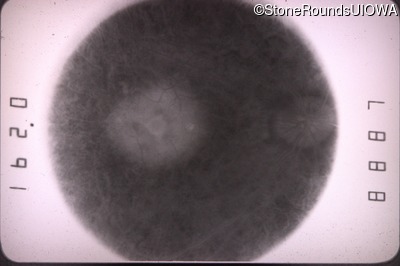

Fundus Photography - Right - 20/70

Exemplar